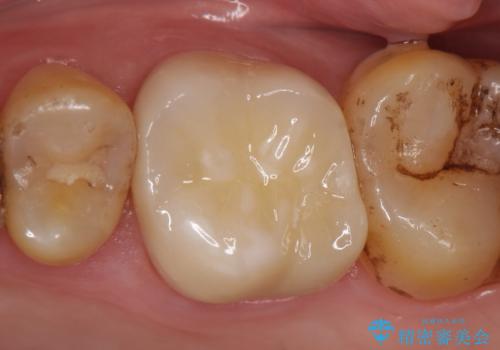

診査の結果左上6は失活していたため、根管治療を行った後にオールセラミッククラウンによる補綴を行いました。

今回用いたオールセラミッククラウンは、ジルコニアフレームという白い素材の上にセラミックを盛っているため審美性が非常に高いのが特徴です。

またジルコニアは人工ダイヤモンドの材料にも使われているほど高い強度を持っており、そのためオールセラミッククラウンは審美性だけでなく、奥歯やブリッジの補綴も可能なクラウンです。